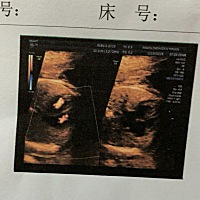

请问这是双胞胎吗,不懂看